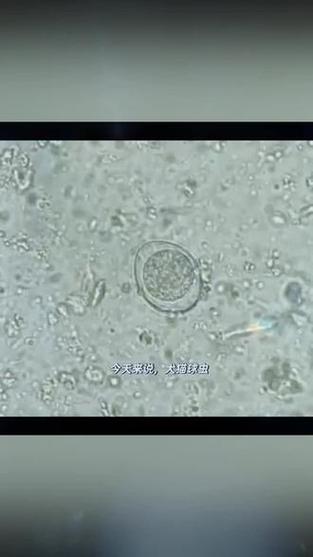

狗狗肚子里有球虫拉肚子多久才好

狗狗肚子里面有球虫拉肚子吃了药以后一天就可以缓解,一周以后可以杀死完球虫。狗狗患球虫病通常表现为出血性肠炎,狗狗会出现拉稀、脱水、贫血、消瘦、衰弱甚至粪便带血,严重的会出现死亡。一旦发现狗狗患球虫病,应该及时就医,避免狗狗发生意外。

幼犬患上球虫疾病,一般需要治疗一周的时间才可以逐渐地恢复正常。球虫感染并不是普通的寄生虫感染,相对比较来讲,治疗更困难。如果狗狗呕吐、腹泻的症状比较严重,需要考虑静脉输液配合治疗,防止幼犬出现脱水以及低能量的情况发生。

狗球虫一般治疗几天能好啊 球虫的治疗周期比较短,一般轻度的球虫通过合理地治疗会在一周内康复。球虫属于一种十分常见的寄生虫,临床上主要使用磺胺类药物驱杀。球虫感染的临床症状包括腹泻、粘液便、血便等症状,但是对狗狗的威胁不太大。最后,狗狗球虫要加强营养,增加机体的抗病能力。

狗狗球虫治疗后一般在7天左右就能恢复。第狗狗球虫轻度感染的,一般不表现临床症状。第严重感染的,一般在感染后三到五天左右出现排稀便或者带血,不爱吃饭,精神差。第感染经一周的治疗临床症状会消失,渐渐会康复的。

狗狗球虫吃药多久会好 球虫吃药一周症状会明显改善,一个月左右就可以痊愈。狗狗球虫病是由于球虫寄生于狗狗的大肠、小肠表面引起的出血性肠炎。一般会表现出:发热、食欲减退、消化不良、腹泻、粪便稀薄混有粘液、甚至血便、贫血,脱水等情况,严重的话可能会导致死亡。